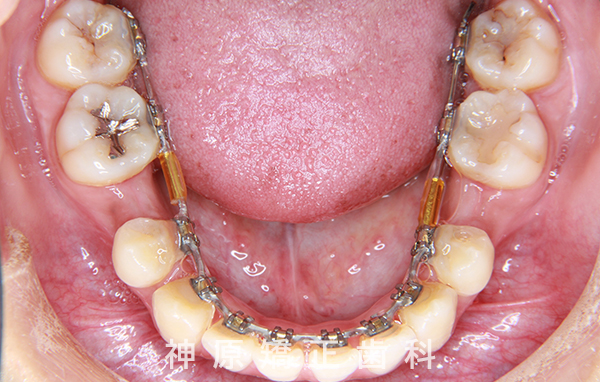

マルチブラケット装着1年後